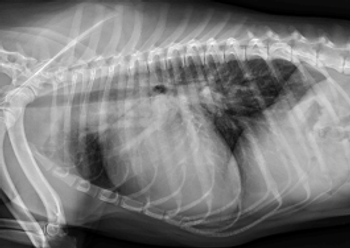

Congenital defects that affect the canine heart have hallmark signatures traceable on puppy exam. Understanding the subtle differences in how they present enables the veterinarian to bring clarity and hope to a dog born with a faulty heart.